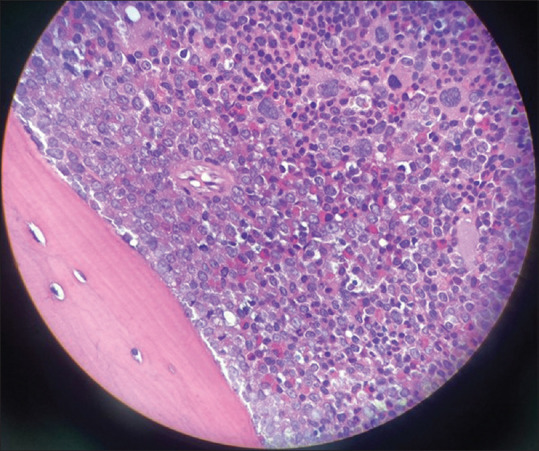

Chronic myeloid leukemia (CML) is a malignant proliferative disorder involving the bone marrow and lymphatic system. Retinal involvement is a rare form of presentation in patients with CML. We report a case of a 49-year-old woman who presented with an acute bilateral visual disturbance. Her initial visual acuity was 20/20 in both eyes. Fundus examination revealed multiple yellowish retinal infiltrates, vascular sheathing, and peripheral sclerosed blood vessels. Fundus fluorescein angiography revealed bilateral peripheral retinal ischemia. Optical coherence tomography of the macula showed varying sizes of hyperreflective lesions distributed within the inner and outer retinal layers and in the subretinal space. Systemic workup revealed marked leukocytosis, and bone marrow biopsy revealed CML. Patients with CML can rarely present with ocular symptoms. Early recognition and prompt referral are crucial in lifesaving.

慢性髓性白血病(CML)是一种累及骨髓和淋巴系统的恶性增生性疾病。视网膜受累是 CML 患者的一种罕见表现形式。我们报告了一例因急性双侧视力障碍而就诊的 49 岁女性病例。她最初的双眼视力为 20/20。眼底检查发现多处淡黄色视网膜浸润、血管鞘和周围硬化血管。眼底荧光素血管造影显示双侧周边视网膜缺血。黄斑的光学相干断层扫描显示,视网膜内外层和视网膜下间隙分布着大小不等的高反射病变。全身检查发现白细胞明显增多,骨髓活检显示患有慢性骨髓性白血病。CML 患者很少会出现眼部症状。早期识别和及时转诊对挽救生命至关重要。